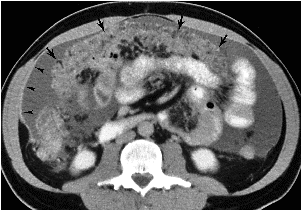

arrow=omental cake.

arrow head=irregular thickening and enhancement

of peritoneum.

massive ascites.